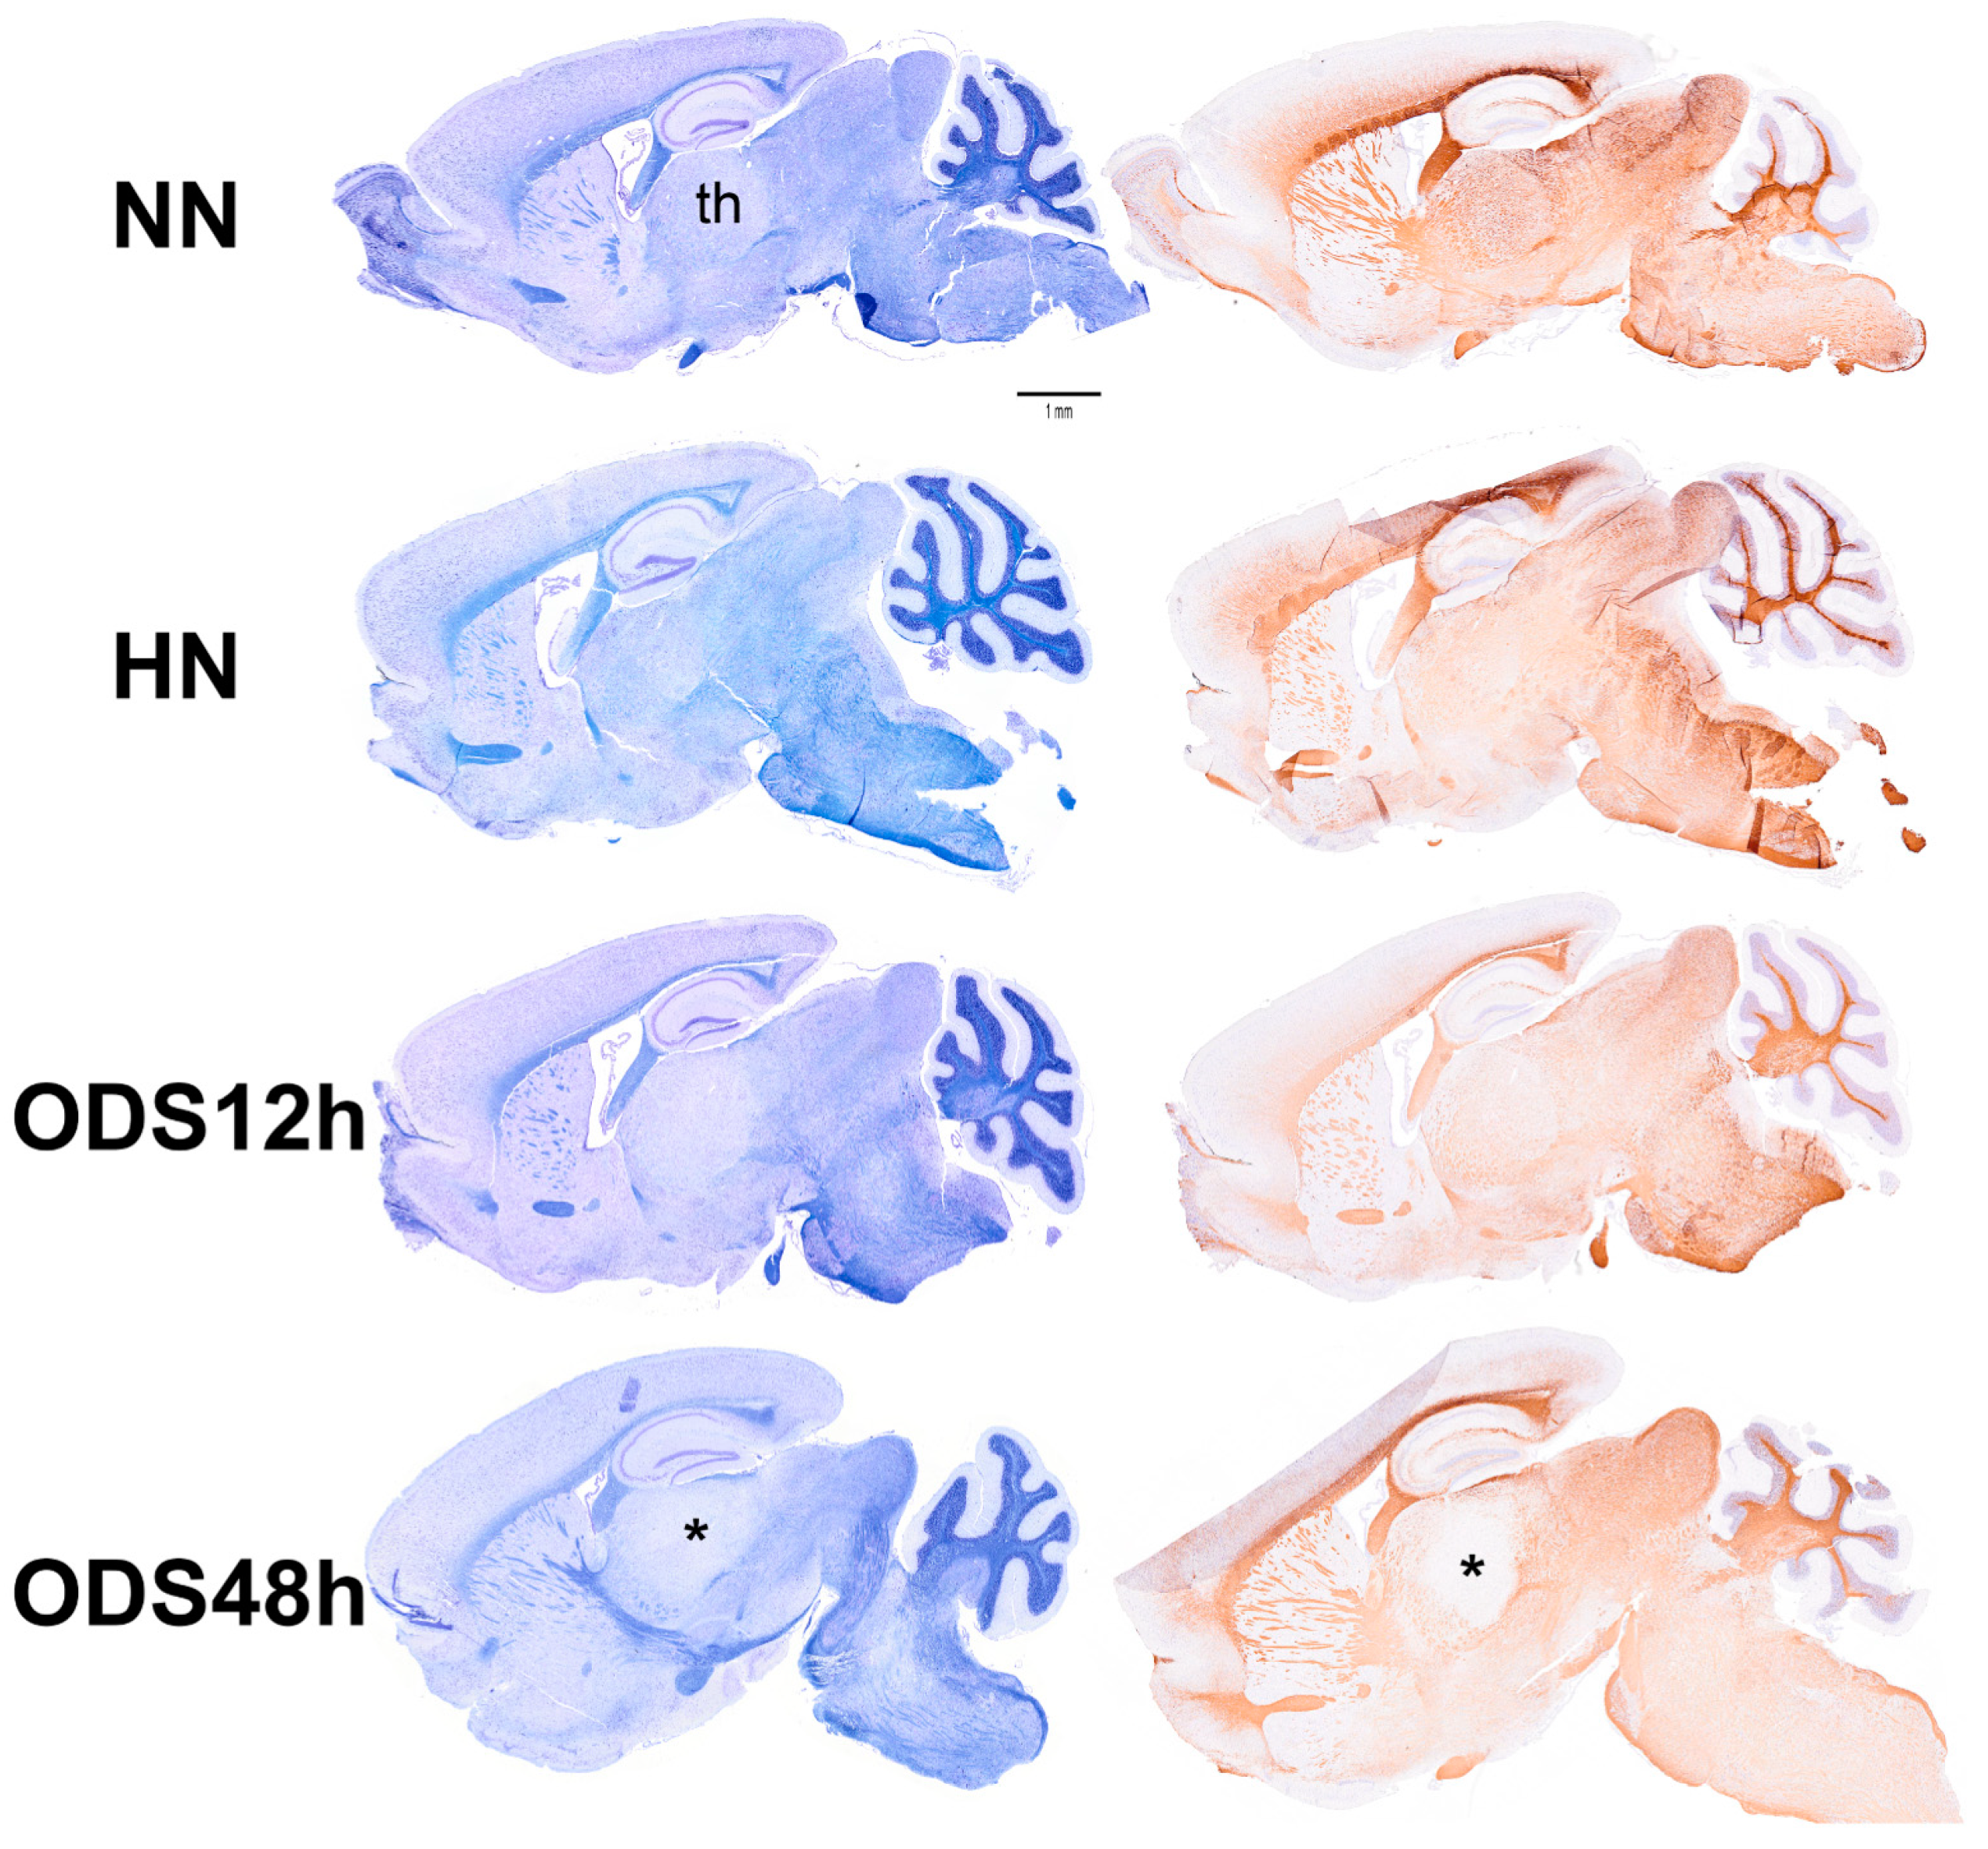

Reviewing micrographs obtained from past data of ODS along with these observations, the murine CNS thalamic region investigated at the time lapse ODS12h can be exemplified where an approximate surrounded and underlined part corresponded with that part which underwent demyelination, as shown in Figure 8A. There, an ODS core area with wasted neuropils showing among its spongy landscape aspect can be seen. In the immediate outskirts, some neurons can be found with LM (Figure 8B) and parts of them were still recognized with TEM (Figure 8C). As shown, in this latter micrograph, two adjacent ODS core neurons demonstrated their necrotic deterioration due to irreversible injury, as their heavily damaged morphology demonstrated nuclei that underwent chromatolysis, revealed by diluted chromatin or remnants whose nucleoli had vanished leaving vacuolated neuroplasms. There, a loosened endoplasm, and several lysosomal and lipofuscin bodies remained. Additionally, when a satellite oligodendrocyte was still recognized, it was as a shrunk, lytic deteriorated body that bore a compacted necrotic nucleus. Within 100–150 µm, the distance away from the worst core damage of the ODS epicenter made of deteriorated neuropils, some of the nerve cell bodies displayed resilience by showing remaining funnel-shaped to elongated shaft-shaped projections issued from their perikaryal zones and, in the best findings we were able to observe, extensions ranging from 2.5 to 15 µm in length (Figure 6, Figure 8, Figure 9, Figure 10, Figure 11, Figure 12, Figure 13 and Figure 14), also evidenced by the ARL13B labeling (Figure 3, Figure 4, Figure 6A, Figure 13A and Figure 14A). At first, micrographs collected with TEM showed numerous granules in these extension that corresponded with the high ribonucleoprotein content associated or not with elongated cisterns of endoplasmic reticulum reaching the core of these axon extensions and, while reaching the funnel constriction segment, the heavily proteinaceous content revealed numerous paraxial and parallel neurotubules (Figure 8D,E). An enlarged view in Figure 9 seems to carry the fine structure aspect of this growth extension of the axon hillock, known as the axon initial segment (AIS) where innumerable proteinaceous components, including neurotubules and associated cytoskeletal macromolecules, appear arranged in periodic rows along and perpendicular to or encircling the cylindric AIS shape and neurolemma can be viewed. The neuroplasm itself, with an enlarged view (Figure 9 insert), can show an underlined parallel concentration of particulate proteins that could be called a sub-neurolemmal structure, further suggesting the unique and crowded peculiar architectural cytoskeletal components necessitated to construct and grow this special segment of the nerve cell body extensions.

2.5. ARL13B Label in ODS48h: LM and TEM: A Primary Cilium Emergence

The thalamic neurons located adjacent but at less than 100 µm distal from the necrotic core ODS, as seen in Figure 8A–E, and more clearly in Figure 9, can be recognized from their shape, using LM, as a large pale nucleus with indent(s) that reveal an evident stained nucleolus and, with TEM, the same highly contrasted, large nucleolus shows large amounts of accumulated granular transcripts (as granular component) accompanying the dense and fine fibrillar components of the chromatin distributed throughout the very active nucleoplasm (Figure 9A, Figure 10A, Figure 11A and Figure A2). At first glimpse, the adjacent neuropil and the satellite oligodendrocytes appear typically located attached to neurons as satellites but, with TEM scrutiny, these were mostly damaged by ODS cell stress and are surrounded by large neuropil intercellular spaces throughout and possess other cells’ and myelin remnants, implicated after leakage of blood fluids, plasma with serum, contributed via the small regional necrotic cells to the archetypal term of ‘liquefaction necrosis’. However, within this ODS damaged zone outskirts, among some degraded and corpses of neuropil, resilient neurons found in the outskirt region were marked by large euchromatic nuclei and active nucleolus; they showed numerous ribonucleoproteins but also reveal through their fine structure that they possess delicate but clear-cut primary cilia (Figure 10A,B). Each cilium length ranged from 4.5 to 6.0 µm long and width from 0.2 to 0.25 µm that is filled with a core of granular cytoplasm and microtubules. The example illustrated shows its transition zone cell attachment consisting of a narrow transition segment or ‘neck’ of about 0.15 µm in width, that is tied by basal fibrillar materials, and forms a ciliary pocket or cove-like space of the plasma membrane. Within the neuroplasm, obscured by numerous ribosomes, a microtubule fascicle and other subcellular filaments can be barely seen originating from the adjacent perikaryal region and reaching the basal side of the primary cilium whose random sections constitute a sort of ‘hub’ region, probably endowed by a centriolar piece structure in some other ultrathin section. In Figure 10A–C, adjacent to the primary cilium, one can note filopodia-like extensions, as these could also be relevant to this rejuvenated change associated with cell resilience (Figure 10C). Other neurons of the same region (Figure 8D,E), at low magnification, bear an axon hillock that becomes like a funnel, similar to the neurons, and more distally located away from the core ODS damages, as shown in Figure 11, Figure 12, Figure 13, Figure 14 and Figure A2, displaying axon hillocks and an axon initial segment without any ciliation. Underlined by ocher yellow (Figure 12A) and enlarged in Figure 12B, the Golgi apparatus saccules characteristically erupt in numerous small vesicles (50–70 nm diam) that accompany ribonucleoprotein particles (mainly RNAs), revealing swirled ribbons of polysomes in places. Vesicles and particles appear to redistribute into the AIS, showing as an initial squeezed cylindric shape aligning the entered neurotubules into a paraxial to parallel orientation congested by one or more long, twisted mitochondrion. Both mitochondria profiles and inner neurolemma leaflet can be decorated by small round to elongated vesicles while the outer leaflet has typically no myelin. However, some synaptic contacts are noted amongst end-feet profiles of astrocytes, recognized by their highly contrasted granules of glycogen content (Figure 12A,B).

A cylindrical extension of the axon hillock morphology of the same diameter and of variable length according to its CNS location, development stage and maturity as well as species [159] has been named the ”axon initial segment” or AIS. The AIS fine morphology was first reported in [159,191,192] and many other publications, including recent recurring surveys, due to the progress in an understanding of its molecular components that has ensued [193,194,195,196,197,198,199,200,201,202]. The main characteristic is certainly that its axolemma, free from myelin—as not yet enfolded by the oligodendrocyte extensions—appeared usually as a tubular, shaft-shape that distally extended into the axon proper, the longest extension of most neurons [159,195,203]. The changes in length and maturation of the axon hillock combined with the AIS CNS location seemed to adjust the ion-voltage channel populations and distribution as they can influence excitability [197,204,205]. AIS of the ODS12h and, more evidently, those of HN, ODS12h, and ODS48h revealed morphologic features classically found by other morphologists [159] to be without Nissl bodies; however, here basophilic components were not excluded because, during the post ODS lapses of time investigated after rebalancing osmolality, AIS presented high electron density of ribonucleoproteins that verified abundant translational activities [66], probably like those noted during development. These abundant transcripts, spilling out of the reactivated nucleolus (Figure A2) as in [66], were revealed specifically as many LM molecular markers with high resolution microscopy [206] and biochemical analyses [200]. These ribosomes and polyribosome population dispersed among other organelles, including the mitochondria that showed even in AIS under restoration (Figure 8E, Figure 12A,B, Figure 13C and Figure 14E,F). These observations concurred with those of others because mitochondria were also found with ion beam/scanning electron microscopy (FIB/SEM) in this neurite segment that underwent repairs [206,207,208]. Out of the aforementioned surveys [193,194,195,196,197,198,199,200,201,202], the AIS complex of macromolecular assembly and architecture was progressively deciphered by a few in vivo, organoid, and many in vitro studies from the earliest soma protrusion to form an axon [209,210]. With a survey that quoted more than 45 macromolecular glycoproteins and proteins whose location in the AIS have been individually located, one can summarize the AIS as subdivided into three cytologic concentric layers:

(a) The membrane or axolemma, in contact with the neuropil, and a sleeve of about 100 nm thick neuroplasm (Figure 9, Figure 11, Figure 12 and Figure 13) is different from the AIS core extended in the distal axon. There, the major AIS scaffolding protein ankyrin G (AnkG) and βIV-spectrin interacted with many other proteins of the axolemma, including voltage-gated ion channel sodium ((Nav) that include Nav 1.6, Nav 1.2, Nav 1.1), potassium K(+) (Kv1.1, Kv1.2, Kv1.4, and Kvbeta2) glycoproteins which bestow unique electrical properties of the AIS, whose axolemmal distribution depended on development stage and CNS location [188,193,195,211]. Those channels’ diversity and distribution density remained somewhat unclear [171,182,211,212,213], but are important because the axolemma of the initial segment is where the action potential originated for initiation of neural functioning and regulation. It is similar with Ca2+ subunits and adhesion receptors (e.g., L1 family neurofascin [NF-186]) whose distributions and co-localization also appeared within the phospholipids of axolemma. Those channels interact with the sub-membranous molecular complex layer (see the next paragraph) composed of membrane scaffolds, i.e., cell adhesion molecules and cytoskeletal proteins exhibited a similar dense granular layer as submembranous (Figure 9, insert, and Figure 11B); also seen in the specialized membrane cytoskeleton of the nodes of Ranvier [159,214,215]. Possibly, the heterogeneous vesicles, born out of the RER and Golgi sorting, such as those shown in Figure 10C,D, can confirm those transcripts, translated at the endoplasm membranes and Golgi to be dispatched at their proper docking axolemma and axoplasm sites. Throughout and along AIS external axolemmal leaflet, adhesion, and recognition molecules such as membrane-anchored proteins ADAM22 (disintegrin and metalloprotease), contactin-associated protein-like 2 (Caspr2), transient axonal glycoprotein-1 (Tag1), and the postsynaptic density-93 (PSD-93) can be found.